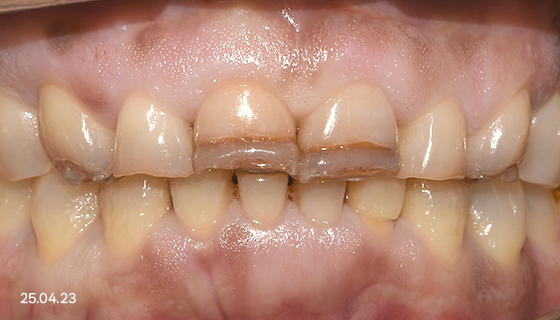

심미 보철 치료

음식을 저작하는 ‘기능’과 눈에 보이는 ‘심미성’을 모두 개선하는 치료를 말합니다.

보통 눈에 잘 띄는 앞니쪽에 많이 진행하며, 크라운, 라미네이트 방식으로 치료합니다.

크라운 방식

손상된 치아를 복원하거나

형태, 색상을 보완하기 위해

새롭게 치아를 만들어 씌우는 방법

라미네이트 방식

치아 겉면을 얇게 갈아 낸 후,

그 위에 얇은 세라믹 판을 붙여

단시간내 심미성을 개선합니다.